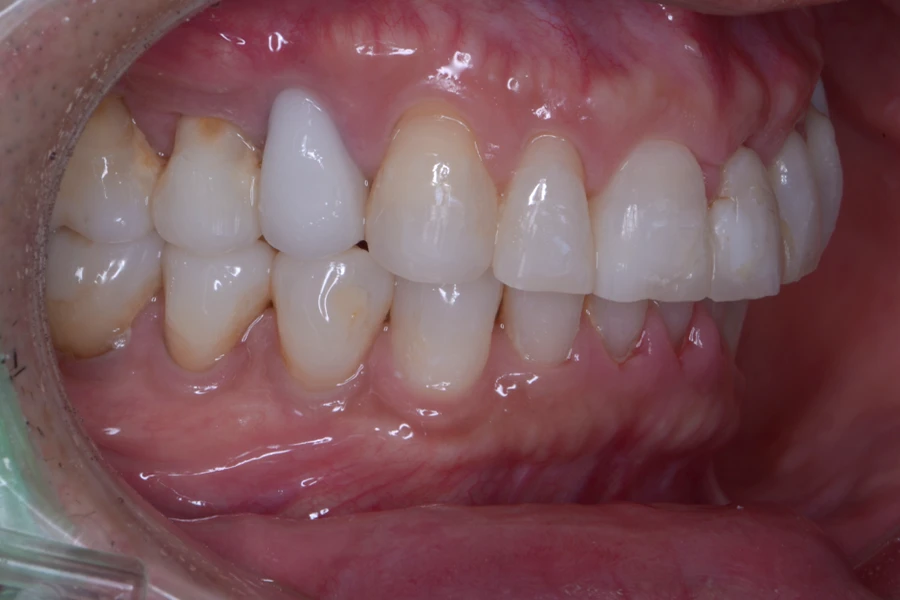

治療後

主訴 インプラント治療後に前歯の形を良くしたい

期間 12か月

費用 40万円(別途調整料)

治療内容 上下顎ラビアル矯正(表側矯正)